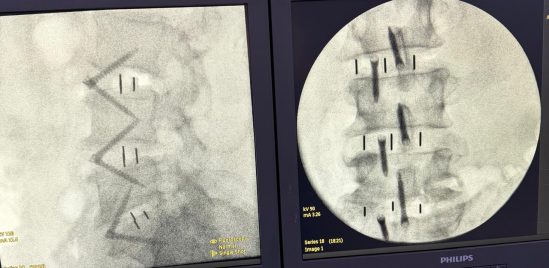

O neurocirurgião Leandro Alcy é referência em Campos dos Goytacazes no tratamento de doenças da coluna lombar e cervical. No Hospital Geral Dr. Beda, ele utiliza, em casos selecionados, a técnica ALIF (Artrodese Lombar Intersomática Anterior), procedimento que acessa a coluna pela região abdominal e exige cuidado no manejo de vasos e outras estruturas anatômicas.

- Descompressão Indireta: Remover o disco doente e substituí-lo por um cage (prótese) maior, o que aumenta o espaço foraminal (onde passam os nervos) e restaura a altura discal.

- Melhor Estabilidade: O cage intersomático oferece uma base sólida, proporcionando maior consolidação da fusão (artrodese).